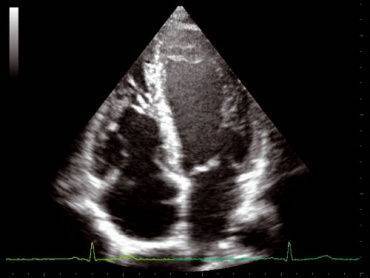

Эхокардиография (ЭхоКГ) — это метод исследования морфологических и функциональных изменений сердца и его клапанного аппарата при помощи ультразвука.

Описание

Эхокардиография, сокращенно ЭхоКГ, — метод исследования сердца, основанный на ультразвуковом сканировании грудной полости. С помощью этого способа проводится диагностика различных заболеваний «двигателя» организма. Данный метод исследования позволяет оценить общие размеры как самого сердца, так и отдельных его структур (желудочки, перегородки), толщину миокарда желудочков, предсердий. Также ЭхоКГ может определить массу сердца, фракцию выброса и другие параметры.